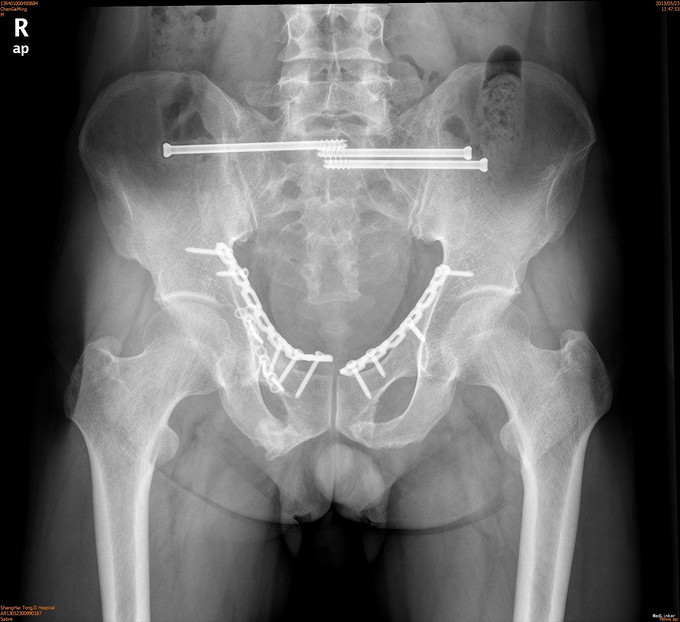

诊断为耻骨上下支骨折,兄弟科室会诊治疗结束后,患者病情稳定,行切开复位内固定术。

1年后随访患者无疼痛,活动可。耻骨上下支骨折ORIF术疗效良好。